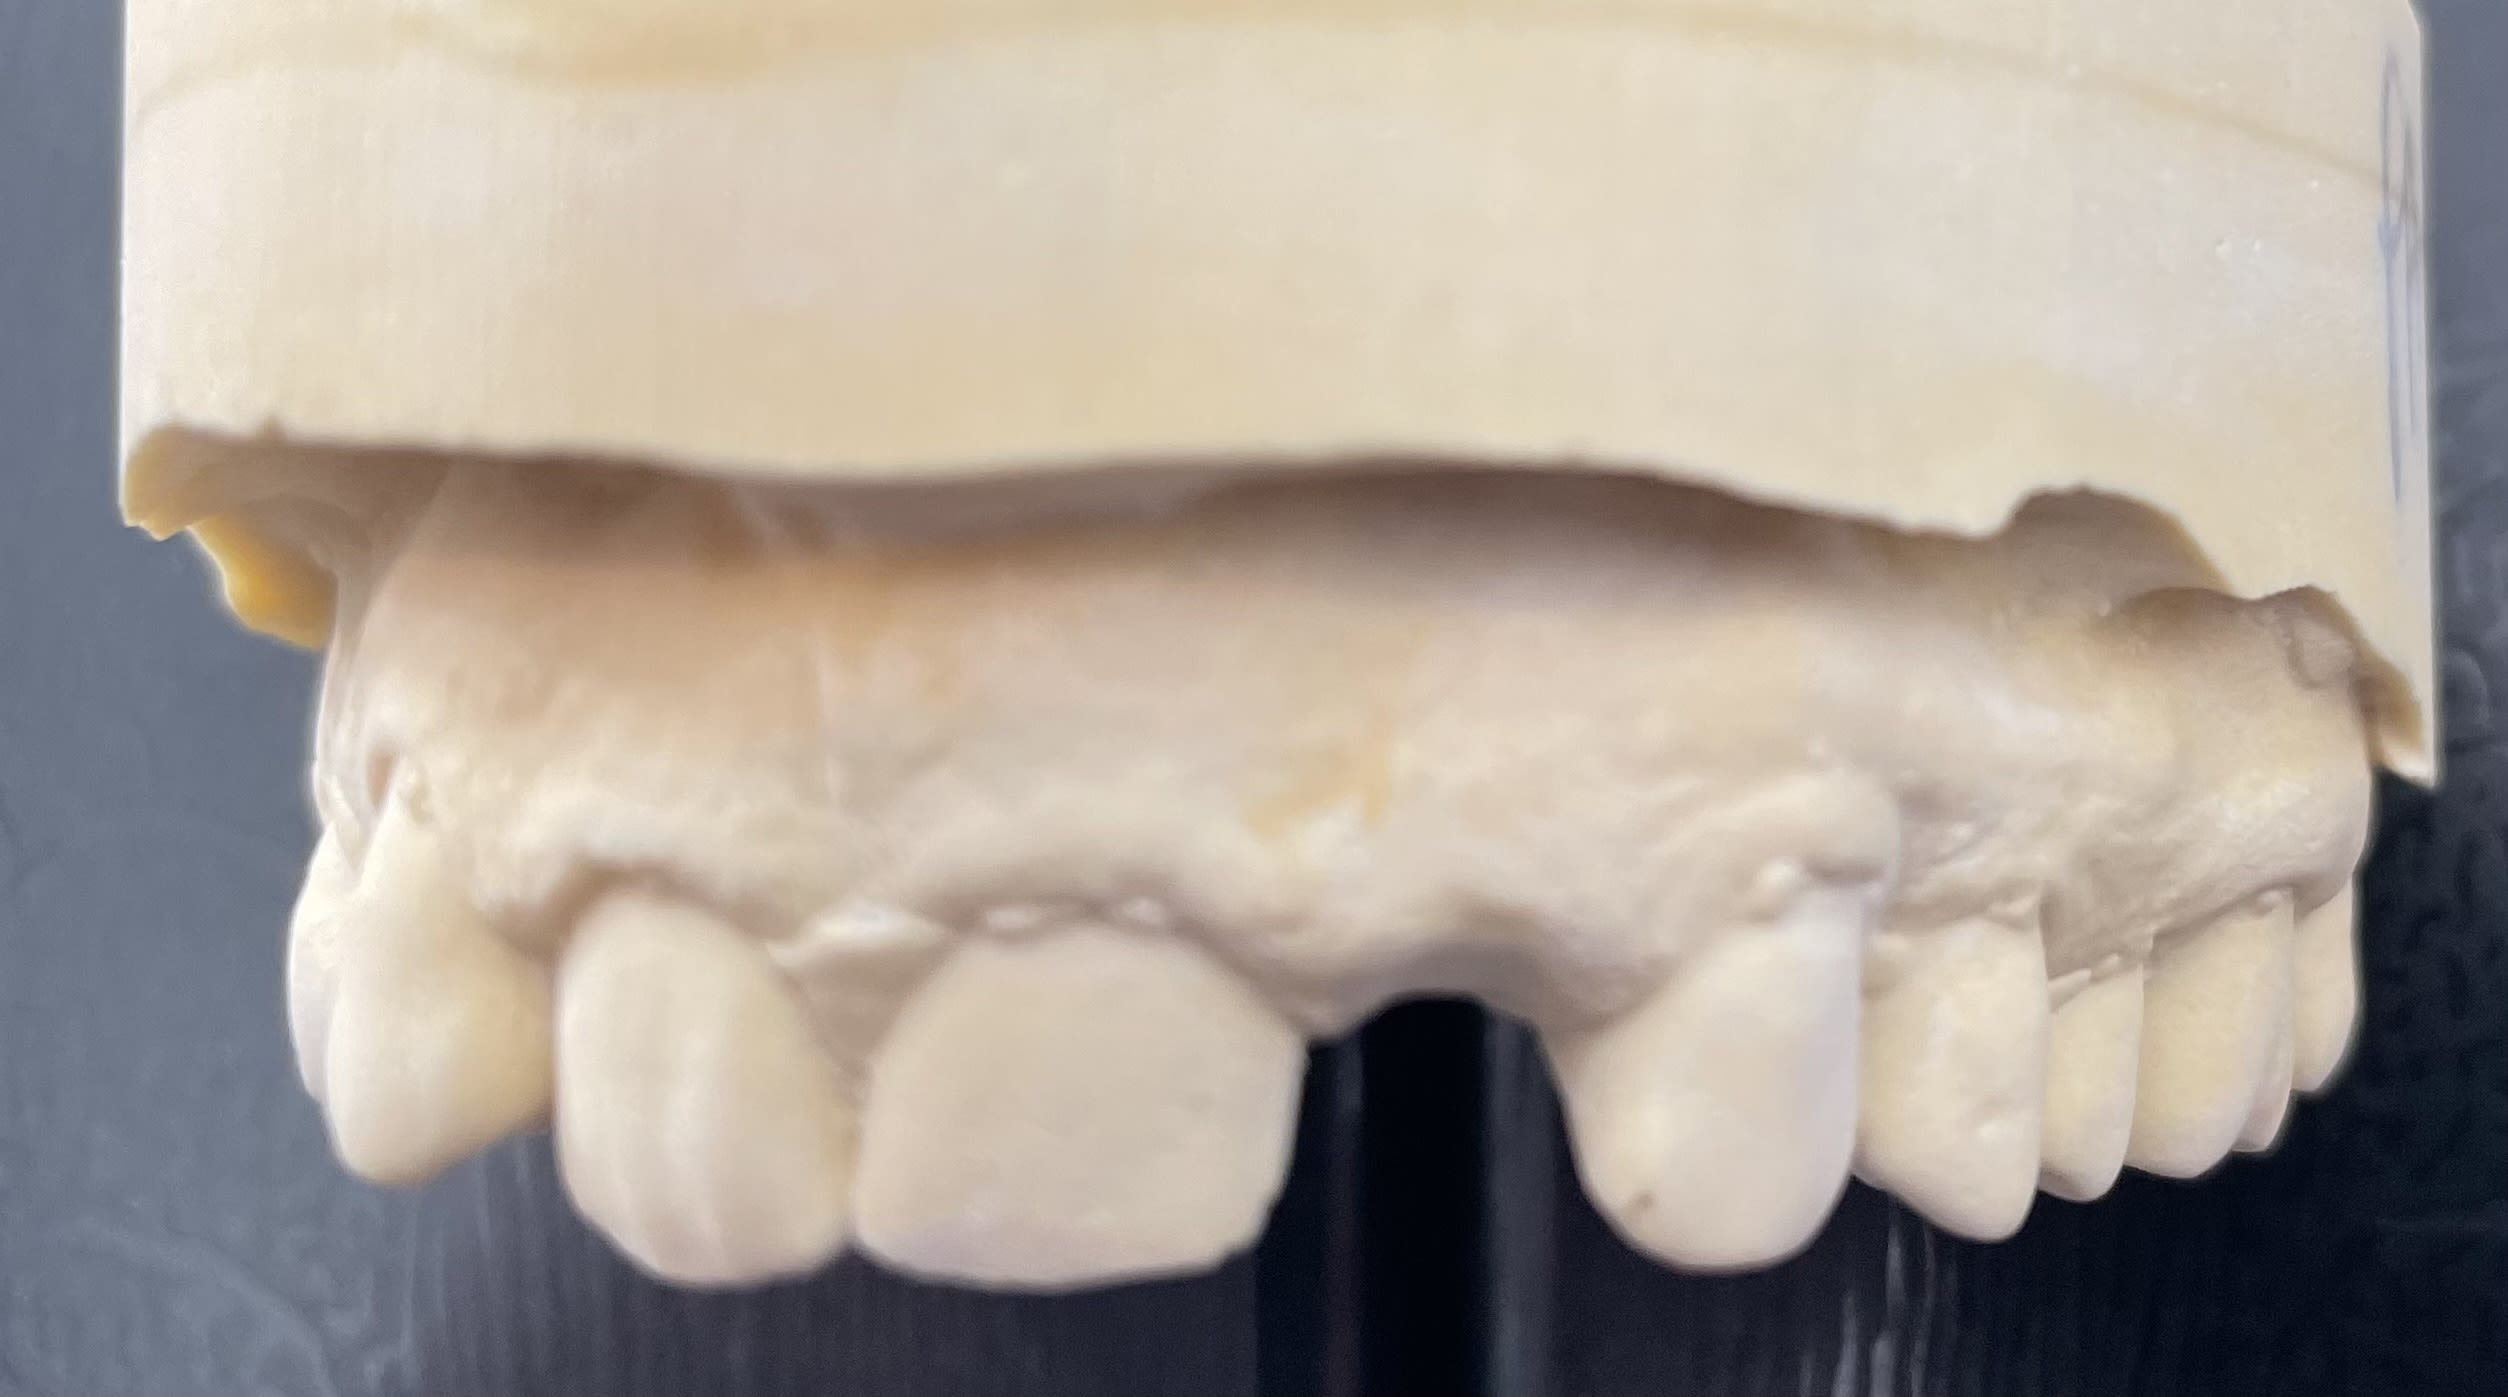

J’aimerais remplacer cette 22 par un implant 3,4 AXIOM PX en extraction implantation immédiate

Seulement j’ai juste 6mm…

Idéalement il te faut 1,5mm de part et d'autre de l'implant

Donc soit tu pose un 2,8 et tu es dans les clous

Soit tu garde un 3,4 et il te manque 0,2mm de chaque côté...en soit pas si déconnant non plus et tu gardes une simplicité prothétique de l'implant standard....

Idem, surtout que les 6 mm c’est en cervical, rapidement ça augmente… avec une mise en charge ( enfin esthétique on dit maintenant) immédiate, tu devrais être plus que bien!

Si tu pars sur du 3,4 a mon avis il faut avoir présent à l'esprit deux choses :

1/Pas de marge d'erreur sur le centrage de l'implant, car sinon c'est pas pas 0,2mm qui manquera d'un coté, mais forcément plus, et ça peut poser problème.

2/Risque de ne pas avoir une belle papille papille gingivale, et peu de marge de manœuvre pour gérer le profil d'émergence dans une zone esthétique.